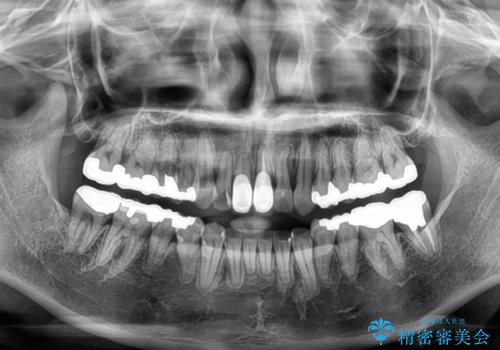

- 前歯のデコボコとセラミッククラウン周りの黒い縁を気にして来院された患者様です。

前歯の黒い縁は、矯正治療後にオールセラミッククラウンにて改善することとしましたが、いち早く目立たなくしたいとのことで、事前に矯正治療用仮歯に置き換えてから矯正治療を開始しました。

前歯を早々に仮歯に置き換えたことで、矯正治療に意欲的に臨んでくださいました。

口元が前方に突出することもなく、綺麗に仕上げることができました。